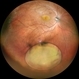

- Traumatic Lens Dislocation

- Traumatic lens dislocation, extraocular